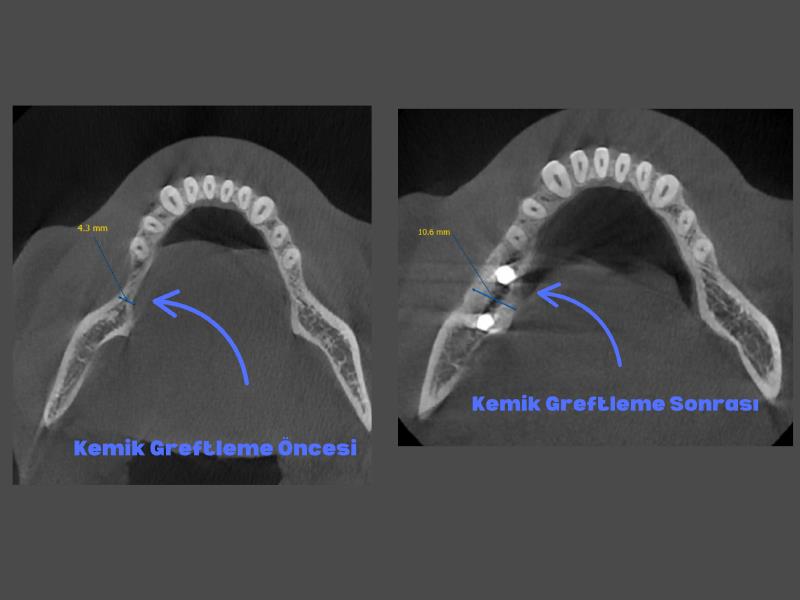

Çene kemiklerinde hacim yetersizlikleri ve kemik erimesi nedeniyle implant yaptıramayan birçok hastamızın tedavilerini, kemik greftleme (kemik tozu uygulaması) ile tamamladık ve böylelikle implant destekli sabit (takıp çıkarma gerektirmeyen)protezler kullanmaya başladılar.

Kliniğimizde kemik grefti tedavisi, eksik ya da yetersiz kemik dokusunu yeniden yapılandırmak için modern ve güvenilir yöntemlerle uygulanmaktadır. Özellikle implant planlanan vakalarda, kemiğin yetersiz olduğu durumlarda kemik grefti ameliyatı ile bölge güçlendirilir ve sağlıklı bir temel oluşturulur.

Diş kemik grefti, çene kemiğinde erime ya da incelme olduğu durumlarda uygulanan bir işlemdir. Bu işlem sayesinde implant tedavisi ve estetik diş uygulamaları için uygun kemik hacmi oluşturulur. Diş kemik grefti ameliyatı, alanında deneyimli uzmanlarımız tarafından steril ve güvenli bir ortamda gerçekleştirilir.